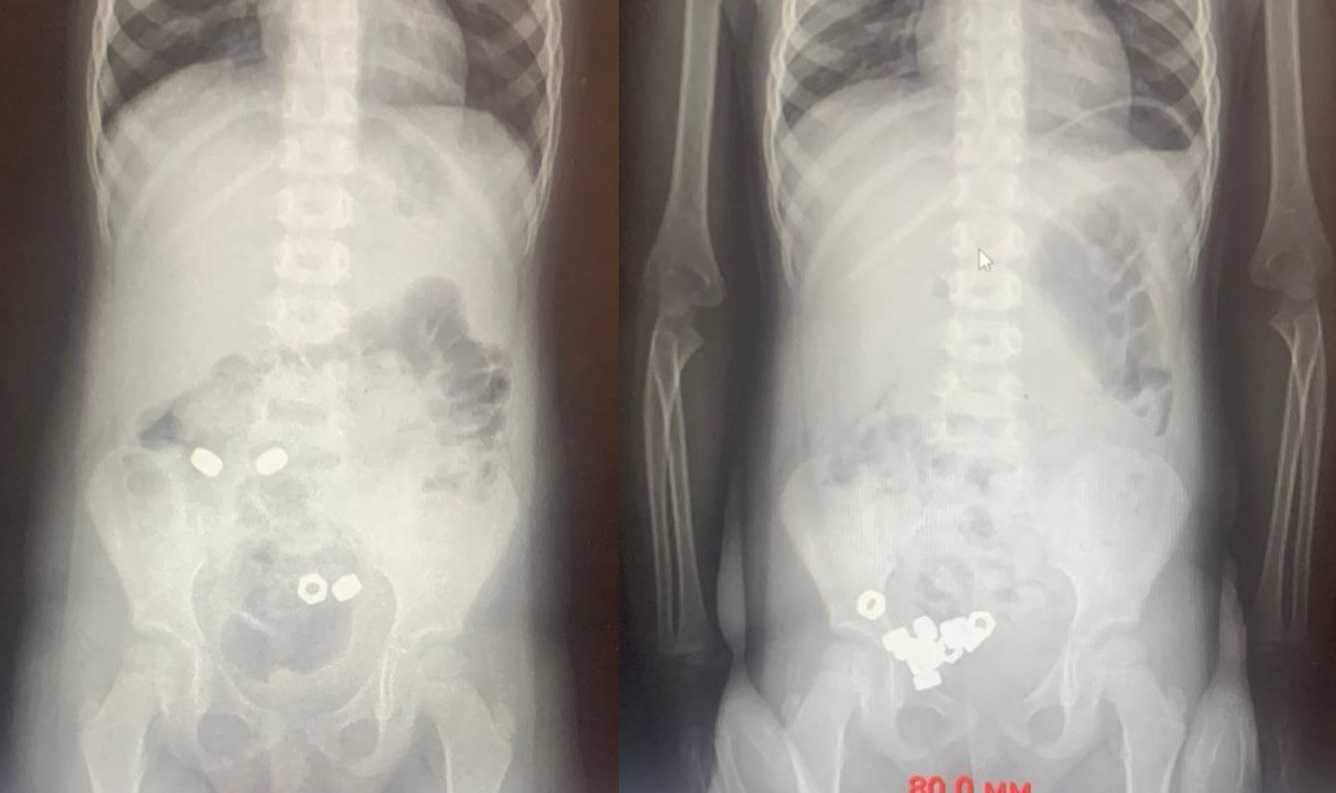

Врачи провели рентген брюшной полости. Тот показал наличие 16 маленьких гаек в желудочно-кишечном тракте ребёнка. Его пришлось госпитализировать для динамического наблюдения: слишком высок был риск развития осложнений.

Поскольку малыш проглотил всё-таки не магниты, медики выбрали консервативную тактику решения его проблемы. Ребёнку назначили диету, покой, контроль стула и рентгенографию в динамике. Этого, надо сказать, оказалось достаточно. К третьему дню все гайки вышли естественным путём. Затем ребёнка выписали из больницы.